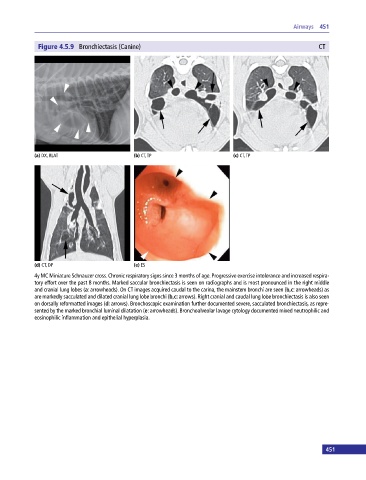

Figure 4.5.9 Bronchiectasis (Canine) CT

(a) DX, RLAT (b) CT, TP (c) CT, TP

(d) CT, DP (e) ES

4y MC Miniature Schnauzer cross. Chronic respiratory signs since 3 months of age. Progressive exercise intolerance and increased respira

tory effort over the past 8 months. Marked saccular bronchiectasis is seen on radiographs and is most pronounced in the right middle

and cranial lung lobes (a: arrowheads). On CT images acquired caudal to the carina, the mainstem bronchi are seen (b,c: arrowheads) as

are markedly sacculated and dilated cranial lung lobe bronchi (b,c: arrows). Right cranial and caudal lung lobe bronchiectasis is also seen

on dorsally reformatted images (d: arrows). Bronchoscopic examination further documented severe, sacculated bronchiectasis, as repre

sented by the marked bronchial luminal dilatation (e: arrowheads). Bronchoalveolar lavage cytology documented mixed neutrophilic and

eosinophilic inflammation and epithelial hyperplasia.